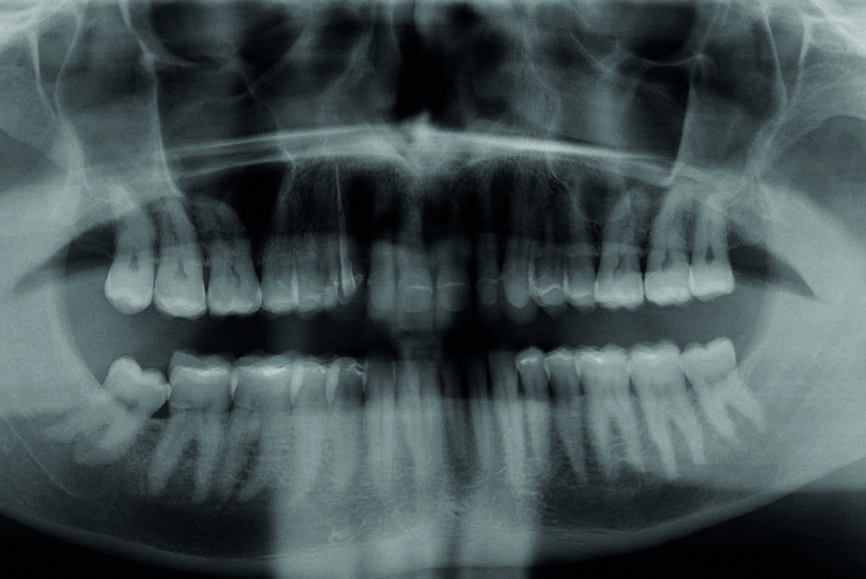

En 2015, un patient de 47 ans se présente au cabinet en raison d’une douleur au niveau de l’ATM. Il a également une préoccupation d’ordre esthétique, car une partie de la facette posée sur l’une des incisives centrales supérieures est fracturée (Figs. 1–3). L’analyse clinique et radiographique (Fig. 4) indique une perte de DVO et de substance dentaire dues au bruxisme.

Fig. 4 : Situation initiale, radiographie panoramique (2015).